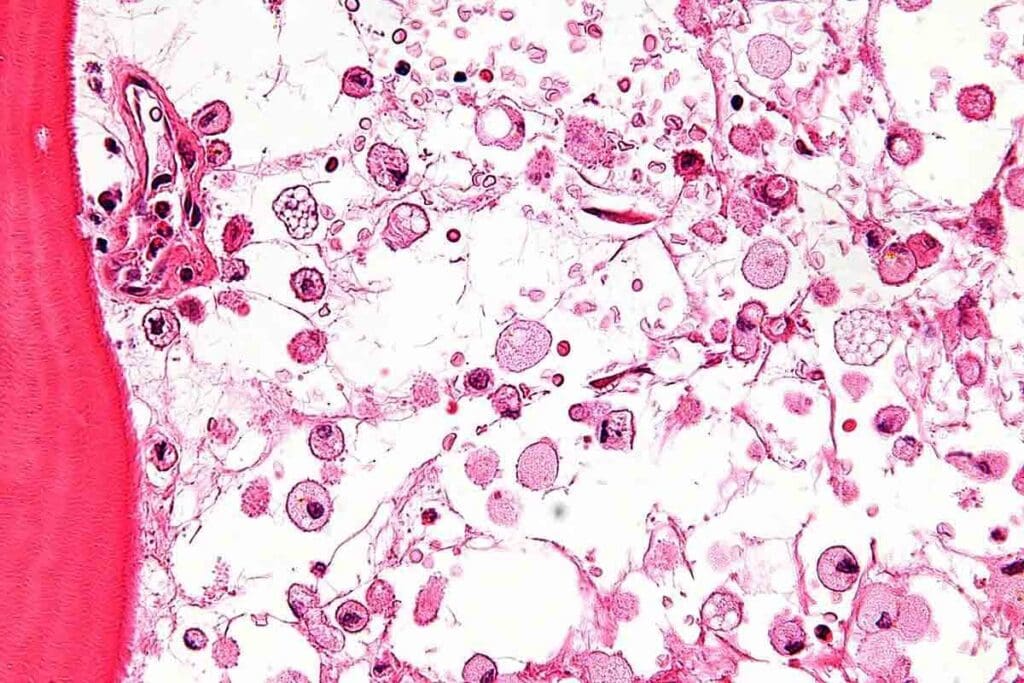

Structure and Function of Bone Marrow

Bone marrow has blood vessels and stem cells. These stem cells turn into all blood cells. It’s supported by reticular cells and fibers, helping it work well. Its main job is to make blood cells through hematopoiesis.

The Process of Hematopoiesis

Hematopoiesis is how stem cells in bone marrow turn into different blood cells. It’s controlled by growth factors and cytokines. This ensures the body makes the right blood cells at the right time.

It starts with hematopoietic stem cells. These can renew themselves and become all blood cell types. As they mature, they specialize, becoming red blood cells, white blood cells, and platelets.